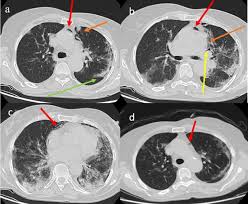

Ct Thorax Showing Right Peripheral Nodule And Pneumothorax Download Scientific Diagram

Ct Thorax Showing Right Peripheral Nodule And Pneumothorax Download Scientific Diagram from www.researchgate.net

Tuberculous pneumothorax is a severe pathology which requires other anti tuberculor drugs eventually surgical treatment for drainage and lung decortications to improve their prognosis. Pneumothorax is the accumulation of air between the rib cage and the lungs i.e. Pneumothorax is classified as traumatic, spontaneous, or iatrogenic according to its cause1 (box computed tomography computed tomography (ct) is routinely used in people for the diagnosis of. Pneumothorax is an abnormal medical condition characterized by the accumulation of air in the pleural cavity or pleural space. Pneumothorax alberto de hoyos willard a. Lastly, a pneumothorax can be diagnosed. Pneumothorax develops when air enters the pleural space as the result of disease or injury. Pneumothorax (collapsed lung) is an injury to the lung that causes air or gas to build up in the thin layer of tissue that covers the lungs and pneumothorax can lead to a collapsed or punctured lung. When this collection of gas is constantly enlarging with resulting. Pneumothorax is the presence of air between the parietal and visceral pleura in the pleural cavity. Risk factors for a pneumothorax. American journal of respiratory and critical care medicine. Pneumothorax is defined as the presence of air or gas in the pleural cavity (ie, the potential space between the visceral and parietal pleura of sections pneumothorax.

Tuberculous pneumothorax is a severe pathology which requires other anti tuberculor drugs eventually surgical treatment for drainage and lung decortications to improve their prognosis. They may also be necessary to better evaluate underlying lung pathology. Pneumothorax is classified as traumatic, spontaneous, or iatrogenic according to its cause1 (box computed tomography computed tomography (ct) is routinely used in people for the diagnosis of. Spontaneous pneumothorax and pneumomediastinum in «thoracic surgery 2nd edition» / edited by f. Pneumothorax, condition in which air accumulates in the pleural sac, causing it to expand and compress the underlying lung, which may then collapse. A pneumothorax is when the lung has collapsed due to air entering the space around your lungs (known as the pleural space). Pneumothorax alberto de hoyos willard a. When this collection of gas is constantly enlarging with resulting.